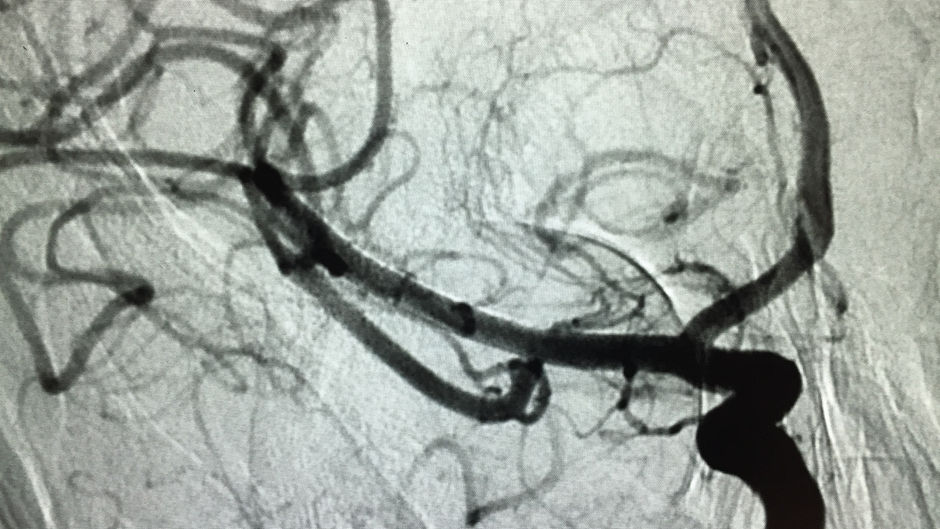

Beyin Anevrizması akım çevirici cihaz ile nasıl tedavi edilir?

43 yaşında bayan hasta sağ kolda kuvvetsizlik ve yüzde kayma şikayeti ile başvurdu.

Beyin damarındaki tıkanıklık kan sulandırıcı ile tedavi edildi.